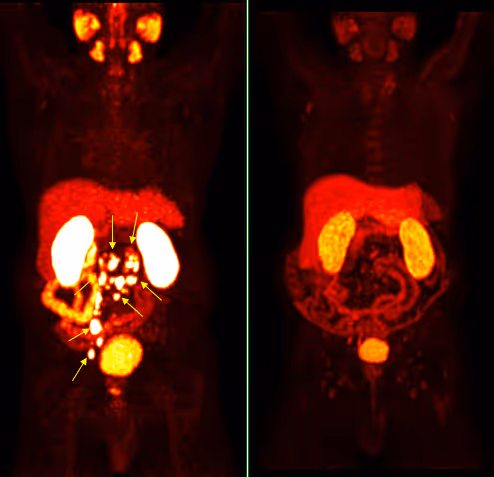

- aktuelle Befunde, insbesondere eine PSMA PET/CT,

Nach dem dritten Zyklus wird üblicherweise eine erneute PSMA PET/CT Untersuchung durchgeführt. Diese sogenannte Interim-Untersuchung dient dazu, das Ansprechen der Erkrankung objektiv zu beurteilen.

Diese Kontrollen können werden in enger Abstimmung mit dem betreuenden Urologen oder Onkologen erfolgen. In bestimmten Situationen kann zusätzlich eine bildgebende Kontrolle, etwa mittels PSMA PET/CT, notwendig sein.